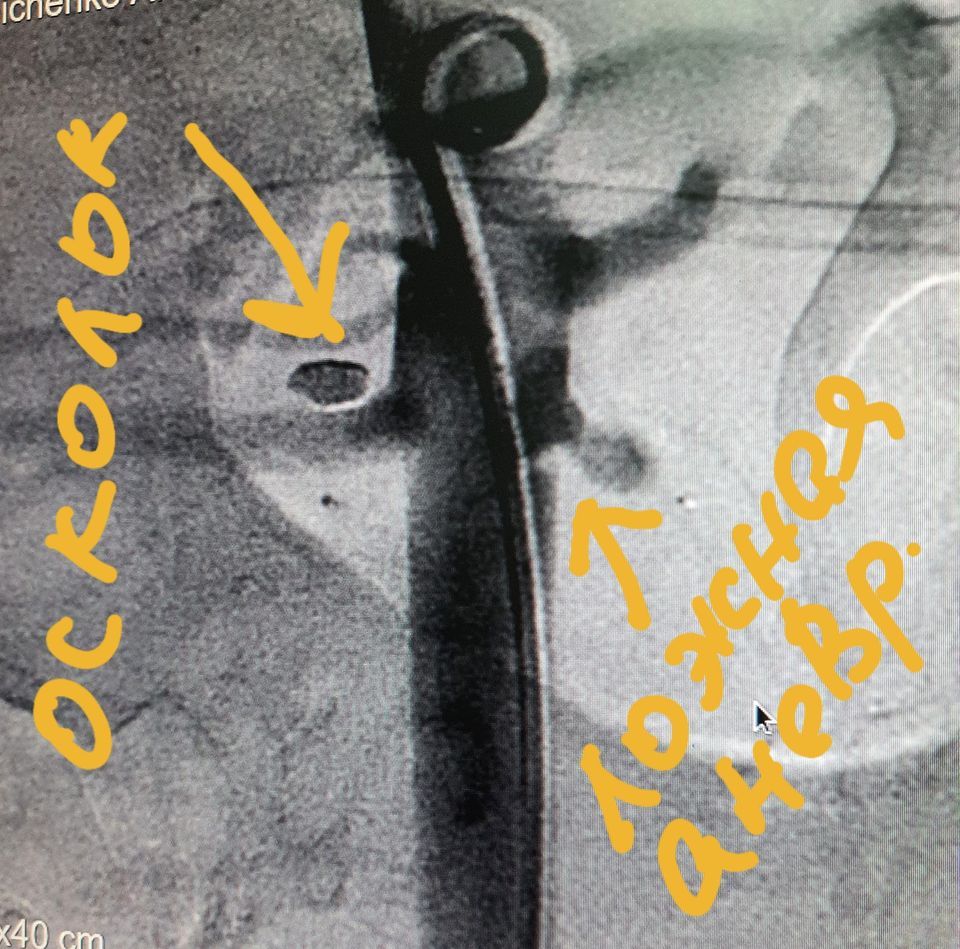

По словам медика, большинство людей с такими ранениями погибают на месте, но 23-летний Алексей вовремя попал к врачам. У него была минно-взрывная травма с повреждением брюшной аорты. Чудом врачам удалось вернуть его к жизни.

Уникальную операцию по пластике аорты и периоперационную интенсивную терапию провели сотрудники днепровской больницы.